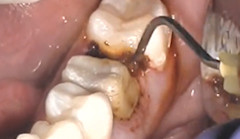

ViscoStat hemostatic's viscous, non-drip formula achieves hemostasis efficiently. The Metal Dento-Infusor™ tip infuses the hemostatic agent into capillaries, forming a cork-like "plug," then wipes coagulum away.

With the Dento-Infusor™ tip, scrub hemostatic firmly against cut bleeding tissues until bleeding stops.